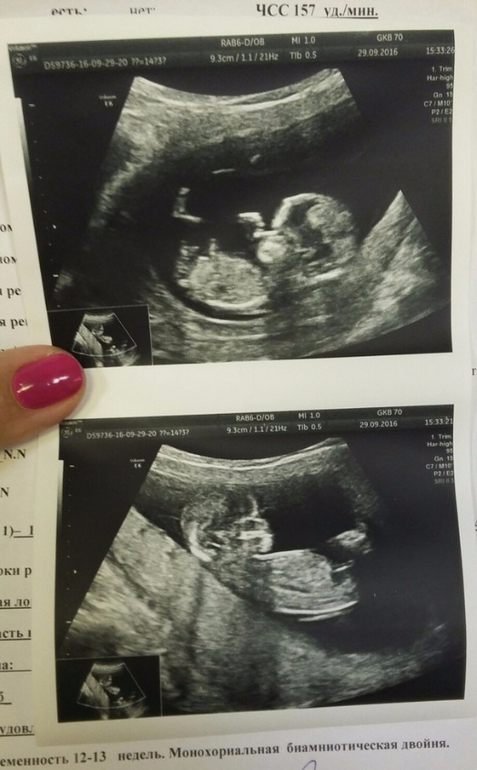

Зачем делают скрининг в 12 недель беременности

Зачем делают скрининг в 12 недель беременности 118 фото